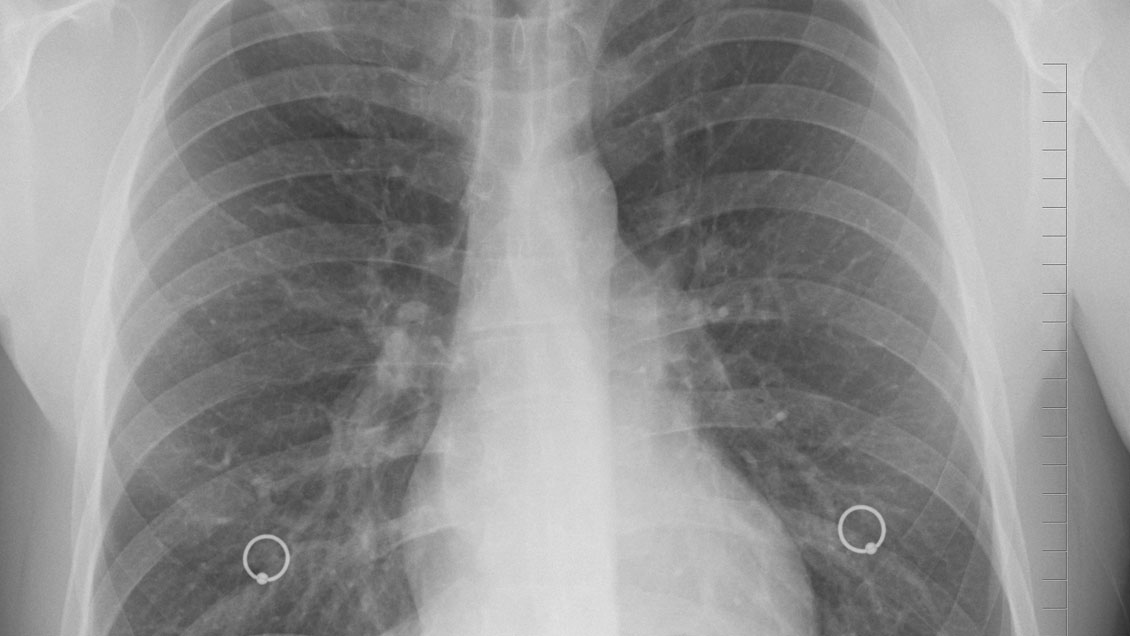

Pixabay (referencial)